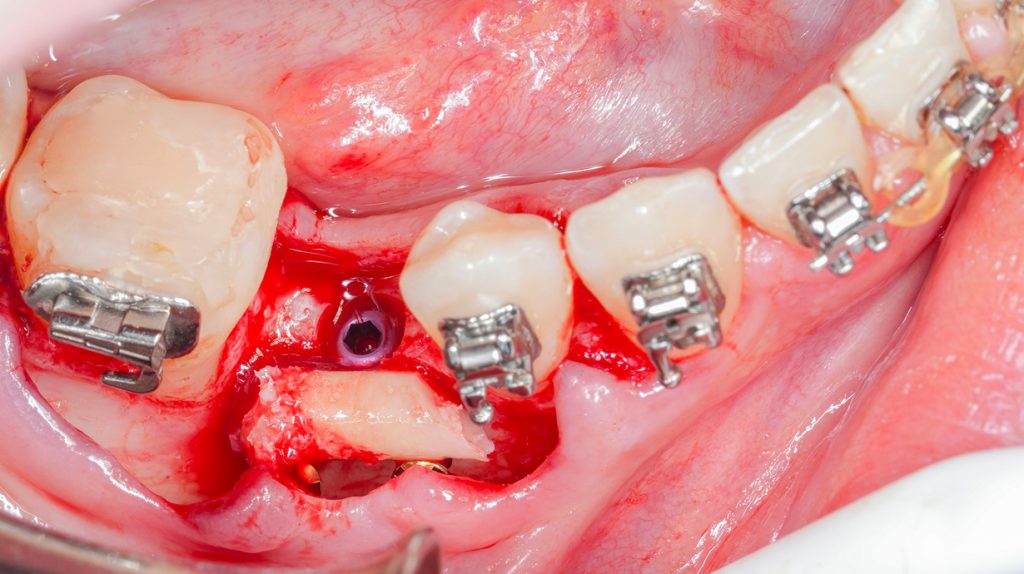

Advanced Bone Reconstruction

Indywidualny szkolenie chirurgiczne dla lekarzy  w formule one-to-one, którzy mierzą się z koniecznością implantacji w warunkach niedoboru kości i chcą podejmować decyzje świadomie, bez kompromisów biologicznych.

Blok kostny, allogenic shell technique, carotta technique czy przeszczep typu triple graft to narzędzia. Największe ryzyko nie wynika z ich użycia. Wynika z błędnej kwalifikacji, niewłaściwego planu oraz niedoszacowania anatomii.

• techniki bloków kostnych w ujęciu rekonstrukcji pionowych i poziomych

• shell technique (autogenne i allogenne)

• IDR | Triple graft | carotta technique

• rekonstrukcje w strefie estetycznej